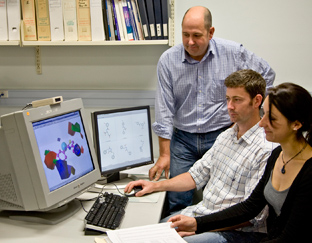

Smarter drug design

An advanced experimental technique linked to high powered computation is becoming an increasingly important tool for MWC researchers developing new drugs.

Virtual screening boosts drug discovery (2010)

A high-powered new virtual environment that allows researchers to screen thousands of molecules as potential new drug leads was launched in 2010, providing a major boost to Maurice